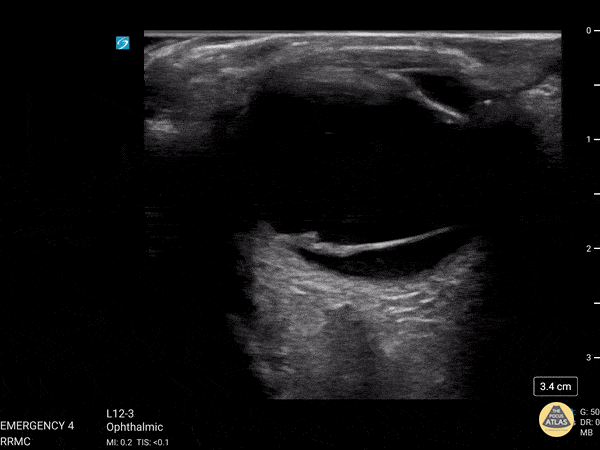

Orbital - Vitreous Detachment

This was from a 52 year old male with a recent surgical history of vitreous detachment that became a retinal detachment. He presented to the emergency room for vision changes in same eye after an object fell and hit his head. Ocular ultrasound was performed at the bedside which revealed a new vitreous detachment. Important to note here that it is crucial to fan/tilt through the entire eye, making sure to visualize the optic nerve in order to differentiate between a vitreous and retinal detachment. In this case, notice how the lesion spotted in the chamber does not connect to the optic nerve, which is consistent with a vitreous detachment. Dr. Christopher Paulo, DO, PGY-1 Riverside Regional Medical Center Emergency Medicine Program (Newport News, VA)